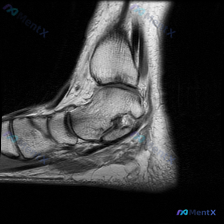

今天遇到一个很有代表性的读片病例,整理了完整信息和分析思路分享给大家。 病例核心信息 本次读片对象是踝关节MRI T1加权矢状位图像,核心疑问是:图像中是否存在软骨异常? 影像详细读片结果 1. 影像质量:图像清晰,解剖层次分明,对比度良好,无明显伪影,可清晰分辨骨髓、骨皮质和软组织 2. 解剖结构...

最近碰到一个很有启发的病例,临床问题是问这张踝关节MRI-T1矢状位影像的观察结果是不是软骨异常,整理一下完整分析思路给大家。 一、影像基本信息 本次仅提供踝关节MRI-T1序列-矢状位单张图像,先把客观阅片结果整理出来: 1. 骨骼结构:胫骨远端、距骨、跟骨、足舟骨及部分楔骨显示清晰,骨皮质连续,...

看到一张踝关节MRI矢状位T1加权影像,问题是观察软骨异常,整理一下读片和分析思路分享给大家。 一、影像基本信息 这是踝关节MRI矢状位T1加权序列,用于评估踝关节及足部解剖结构,先给大家整理读片基础发现: 1. 骨骼结构:胫骨远端关节面形态正常,皮质连续,未见明确骨折;足舟骨、骰骨、跟骨骨质轮廓完...

刚整理完这例踝关节MRI读片资料,分享一下完整的分析思路,这个病例的影像特征其实挺典型的,一起看看。 病例影像基础信息 这是一张踝关节MRI T1加权序列的正中矢状位图像,图像质量清晰,结构对比度好,无明显运动伪影,可以清晰辨认胫骨远端、距骨、跟骨、舟骨等骨性结构。 核心阳性发现 1. 骨信号异常:...

今天遇到一个很有代表性的病例,临床观察提示踝关节存在软骨异常,但拿到的只有一张矢状位T1加权MRI,整理了一下分析思路分享给大家。 病例影像基本信息 这是一份踝关节MRI矢状位T1序列影像,先给大家整理一下已经明确的影像表现: 1. 骨性结构:胫骨远端、距骨、跟骨等所有可见骨骼形态正常,骨皮质连续光...